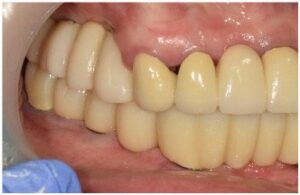

먼저 구강 내를

확인해 보았더니

잇몸뼈 소실이 심해져

치아 뿌리가 노출되어 있는 상태로

Bridge로 연결된 치아 외에도

아래턱 왼쪽 큰 어금니도

동요도가 심한 상태였습니다.

모든 치료가 마무리된

파노라마 사진과

구강 내 사진인데요.

전 > 후